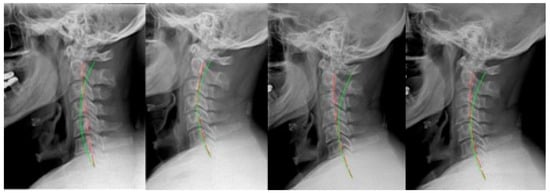

2. Materials and Methods

2.1. Case 1

2.2. Case 2

2.3. Case 3

2.4. Case 4

2.5. Case 5

2.6. Case 6

2.7. Case 7